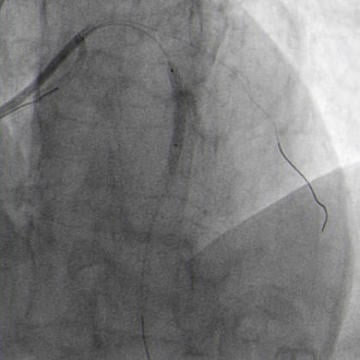

Miracle exchanged with floppy wire to LAD. Guide wires position checked via controlateral injection (Figure 5.2).

Stop coronary flow as soon as possible with balloon inflation technique. Implementation of pericardiocentesis, no Protamine (Figure 7.1).

Quick pericardiocentesis with 6F femoral sheat and balloon dilatation to stop coronary flow (Figure 7.1)